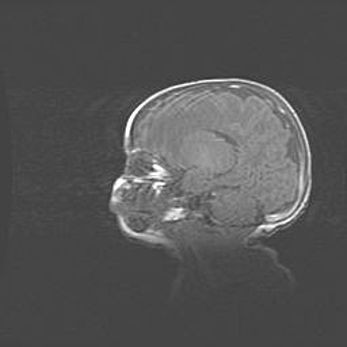

Церебральная ишемия II.

Возраст: 5 дней

Вес: 3400 г

Пол: женский

Окружность головы: 35 см

Срок гестации: 39 недель

Церебральная ишемия – это заболевание, характеризующееся недостаточностью (гипоксией) либо полным прекращением (аноксией) снабжения мозга кислородом по причине закупорки одного или нескольких сосудов. Это приводит к  что метаболическим расстройствам различной степени тяжести в тканях головного мозга, развитию коагуляционных некрозов и гибели нейронов.